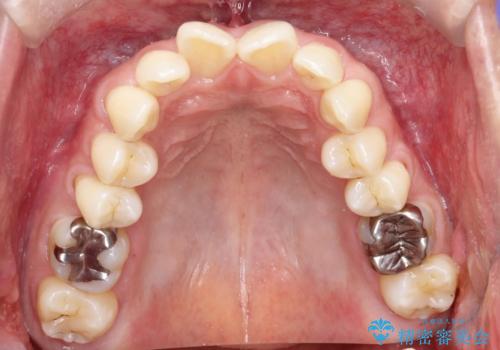

【遠心移動ワイヤー矯正】翼状捻転を治したい

- 前歯の捻れを主訴に来院されました。

顔貌の正中と上顎前歯の正中があっており、下顎は顎位が偏位している状態でした。

小臼歯を抜歯する治療計画も提案しましたが、

今回は患者さんの希望もあり非抜歯にて歯列拡大、遠心移動を行なってできる限り前歯を下げながら配列する治療を行いました。

上顎はリンガルアーチにて遠心移動を行うことで前歯を唇側傾斜させずに配列することができました。